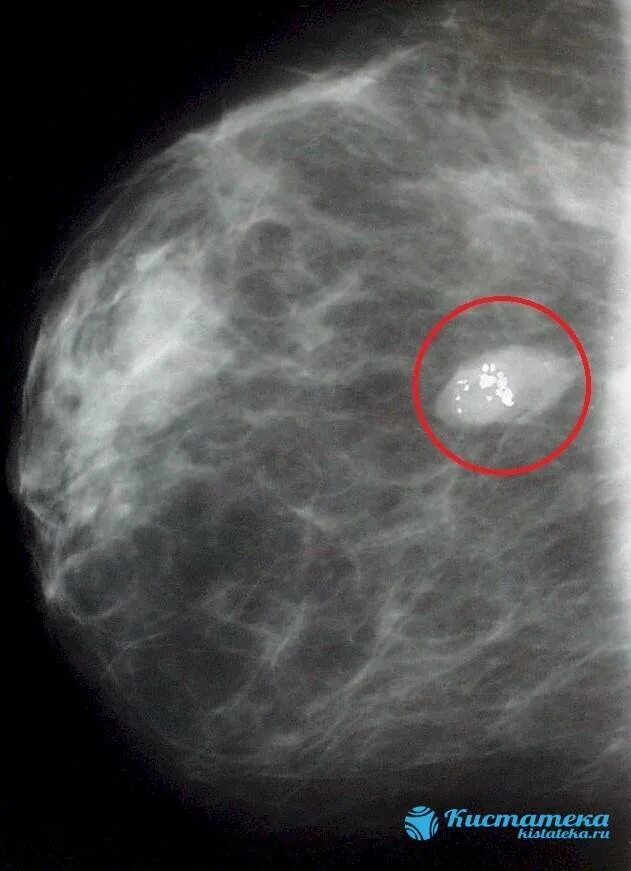

Как выглядит фиброаденома молочной железы